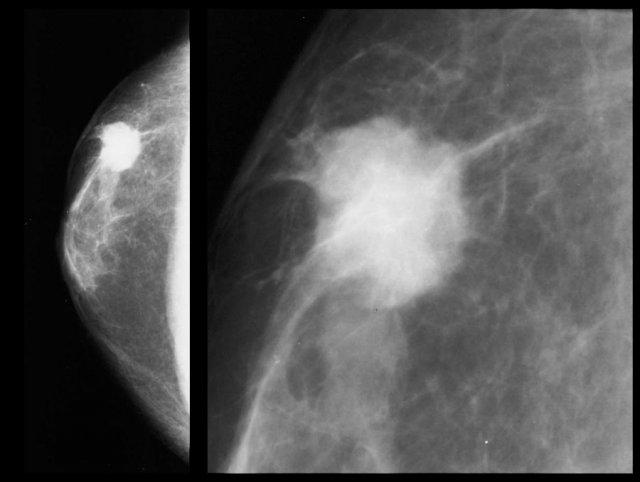

Hình bên trái cho thấy một khối lệch tâm, bờ không đều với các tua gai.

Nếu đây là bệnh nhân nữ, bạn sẽ không gặp khó khăn gì trong việc chẩn đoán đây là ung thư.

Ở nam giới cũng vậy.

Ung thư vú ở nam giới biểu hiện là một khối tròn, bầu dục hoặc bờ không đều.

Vôi hóa hiếm gặp, nhưng khi xuất hiện thì thường thô hơn so với ở nữ giới.

Hình bên trái là một ung thư biểu mô ống tuyến xâm nhập nhỏ, lệch tâm, có vỏ bao.

Hình bên trái là một ung thư biểu mô ống tuyến xâm nhập kích thước lớn kèm theo một số vôi hóa thô, có hình thái lành tính.